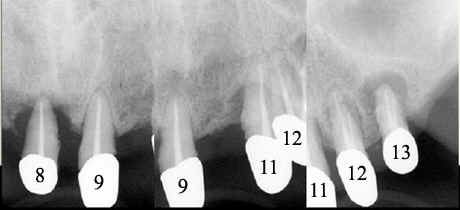

Fig.3

Mr. Fan is 65 years old.  He has had upper and lower overdentures for ten years. Both of them are loose.  He also complains pain associated with upper distal abutments: #8 and 13.  Exam shows generalized advanced chronic periodontits (Fig.1, 2 (upper anterior PAs), 3 (lower anterior PAs).  All of the remaining teeth are nonsalvageable.  The width of the alveolar ridges is adequate (Fig.4 and 7).  The ridge height of the mandible is sufficient, whereas that of the maxilla is questionable (Fig.1).  The patient prefers fixed prosthetics.  We plan to place as many as 24 implants in stages.